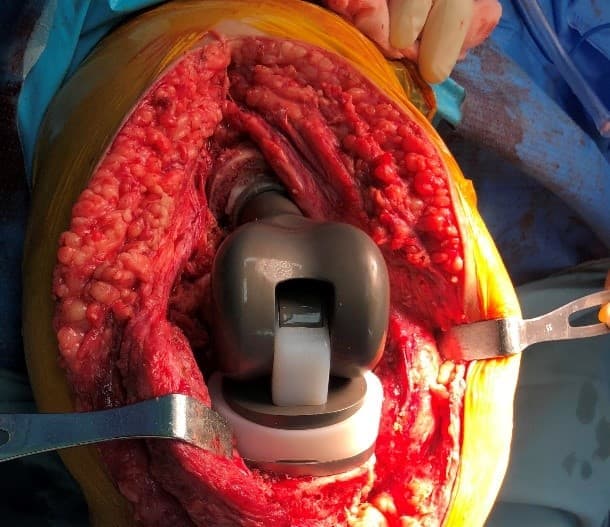

Үе дайрсан ясны анхдагч хавдар, ясны дутмагшлын үед хийгдэх мэс засалimage19

Зураг 2. Мэс заслын үеийн фотозураг. Өвдөгний хиймэл үе – сэргээн засах протез